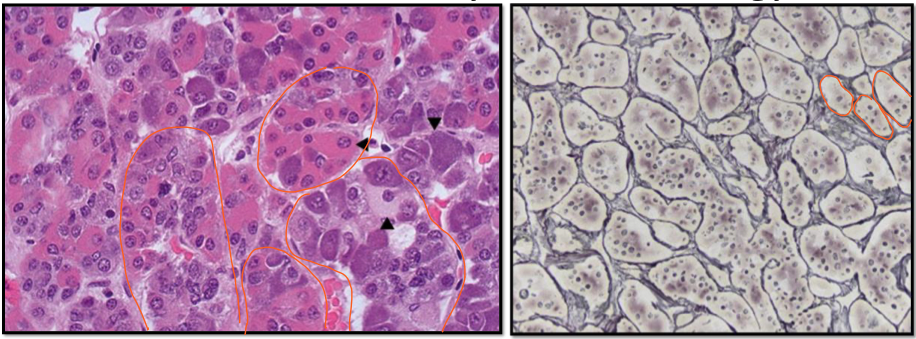

identify two of the three categories of anterior pituitary cells

17

Q

identify the three categories of anterior pituitary cells

histology of anterior pituitary

• chromophils (secretory cells with basophils and acidophils)

• chromophobes (poorly stained cytoplasm)

histology features of pituitary gland

A

• pink acidophils

• purple basophils

• chromophobes

• acinar architecture